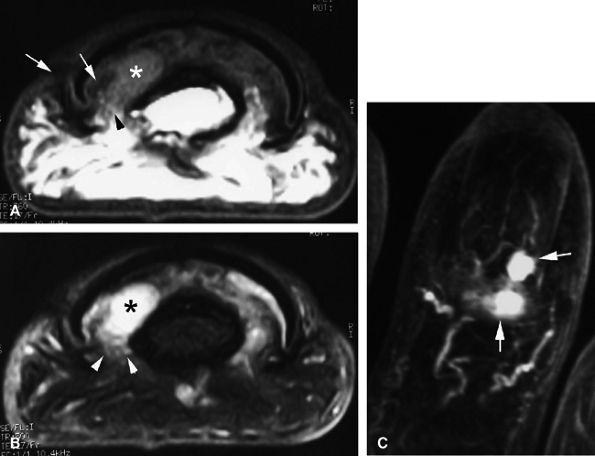

FIGURE 11.43 ● Acute open injury of the flexor pollicis longus tendon. (A) On these coronal post-contrast fat-suppressed T1-weighted images, the distal end of the tendon can be seen at the entry of the digital canal (arrows). (B) The proximal end is seen at the level of the radiocarpal joint (arrows). The tendon gap measures 6 cm. The empty tendon sheath shows significant synovitis (arrowheads in both images).

FIGURE 11.44 ● Acute rupture of the flexor digitorum profundus (FDP) tendon of the little finger in zone II. Coronal (A) and axial (B) post-contrast fat-suppressed T1-weighted images show retraction of a flexible proximal end (arrows) wrapping around the FDS tendon (asterisk).